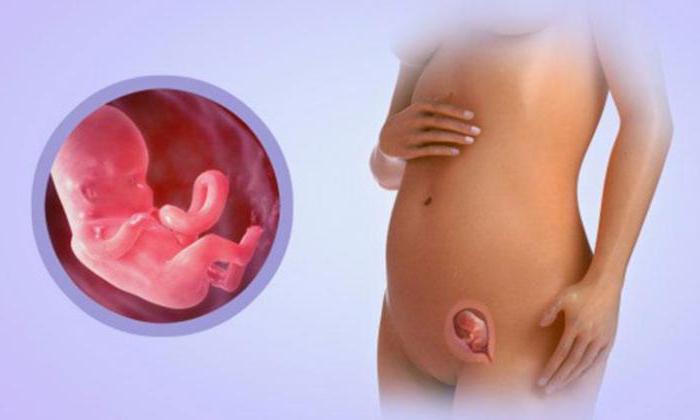

Формирование Плода в Первом Триместре: Важные Этапы